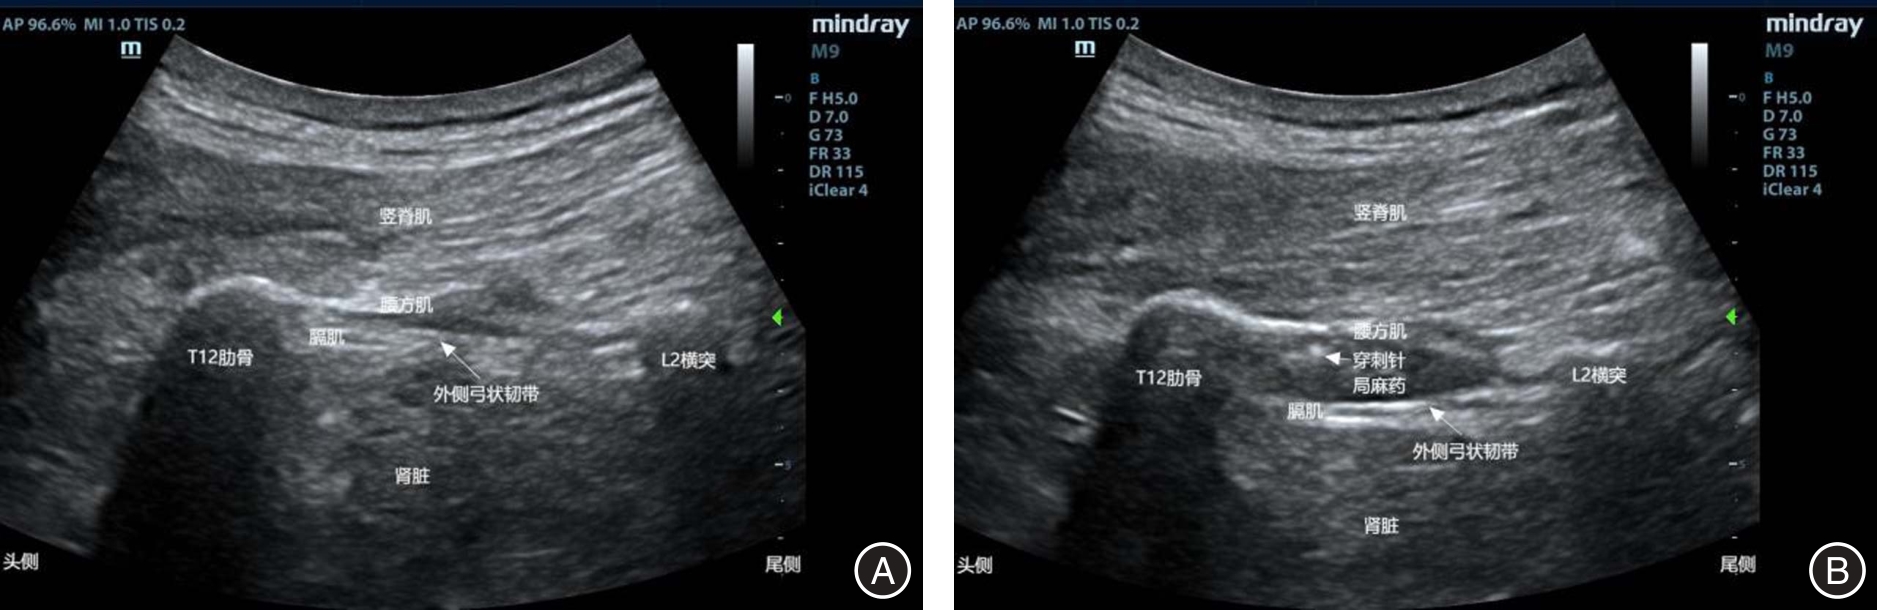

目的 探讨弓状韧带上腰方肌阻滞(QLB-LSAL)与肋缘下腹横肌平面阻滞(STAPB)对腹腔镜结直肠癌根治患者围术期镇痛及术后炎症的影响。 方法 纳入2022年10月至2024年10月择期全麻下行腹腔镜结直肠癌根治术患者102例,两组均行全麻联合神经阻滞,根据神经阻滞方式随机分为弓状韧带上腰方肌阻滞组(Q组,n = 51)和肋缘下腹横肌平面阻滞组(S组,n = 51)。记录麻醉诱导前(T0)、手术开始前(T1)、手术开始时(T2)、人工气腹时(T3)、腹腔冲洗时(T4)、手术结束时(T5)、出手术室时(T6)的平均动脉压(MAP)及心率(HR);记录瑞芬太尼、镇痛泵使用及补救镇痛情况;记录术后24、48及72 h静息及咳嗽时的VAS评分;记录术前1 d、术后1 d及3 d的白细胞介素-6(IL-6)及系统免疫炎症指数(SII);记录术后恢复及不良反应发生情况。 结果 Q组在T3 ~ T6时MAP及HR低于S组(P < 0.05);与S组比较,Q组瑞芬太尼用量减少、镇痛泵首次按压时间延长、有效按压次数及补救镇痛例数更少,术后24 h和48 h静息及咳嗽时VAS评分更低(P < 0.05);与术前1 d比较,两组术后1 d及3 d的IL-6及SII均升高,但Q组低于S组(P < 0.05);与S组比较,Q组首次下床时间及术后住院时间更短,不良反应发生率更低(P < 0.05)。 结论 QLB-LSAL较STAPB可为腹腔镜结直肠癌根治术患者提供更好的围术期镇痛,降低炎症反应,加速术后恢复。

Objective To compare the effects of quadratus lumborum block at the lateral supra-arcuate ligament (QLB-LSAL) versus subcostal transversus abdominis plane block (STAPB) on perioperative analgesia and postoperative inflammation in patients undergoing laparoscopic radical resection of colorectal cancer. Methods In this prospective randomized study, we recruited 102 patients undergoing laparoscopic colorectal cancer surgery between October 2022 and October 2024 under general anesthesia and randomly assigned them to two groups: QLB-LSAL (Group Q, n = 51) and STAPB (Group S, n = 51). Mean arterial pressure (MAP) and heart rate (HR) were recorded before anesthesia induction (T0), before surgical incision (T1), start of surgery (T2), during pneumoperitoneum establishment (T3), during peritoneal lavage (T4), at the end of surgery (T5), and upon leaving the operating room (T6). Intraoperative remifentanil consumption, time to first patient-controlled analgesia demand, and frequency of effective compression and rescue analgesia were recorded. Visual Analog Scale (VAS) scores at rest and during coughing were assessed at 24, 48, and 72 hours postoperatively. Interleukin-6 (IL-6) and systemic immune-inflammatory index (SII) at 1 day preoperatively, 1, and 3 days postoperatively were recorded. Postoperative recovery indicators and adverse events were also recorded. Results Group Q demonstrated significantly lower MAP and HR compared with Group S from T3 to T6P < 0.05). Group Q had significantly lower intraoperative remifentanil consumption, significantly longer time to first analgesic pump demand, fewer effective pump compression, and lower frequency for rescue analgesia requests (all P < 0.05). VAS scores at rest and during coughing in Group Q were significantly lower at 24 h and 48 h postoperatively (P < 0.05). As compared with preoperative levels, both IL-6 and SII increased at 1 and 3 days postoperatively, but magnitude of increase in Group Q was smaller than in Group S (P < 0.05). In comparison to Group S, Group Q demonstrated significantly earlier ambulation, shorter hospital stay, and fewer adverse events (P < 0.05). Conclusion QLB-LSAL is superior to STAPB in enhancing perioperative analgesia, attenuating inflammatory response, and accelerating postoperative rehabilitation in patients undergoing laparoscopic colorectal cancer resection.